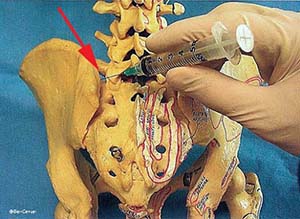

A sacroiliac injection places a pain-numbing medicine and steroid directly into the sacroiliac (SI) joint. There are two sacroiliac joints, one located on either side of the sacrum (see arrow pointing to the left sacroiliac joint). The benefit of this procedure is to reduce inflammation, help confirm the SI joint as the source of pain, and better allow a physical therapist to treat the joint.

You will receive a local anesthetic before a small spinal needle is inserted under fluoroscopic guidance into the SI joint. The procedure takes approximately 15 minutes. The arrow shows the needle within the sacroiliac joint. Once the needle is securely positioned into the joint a small amount of x-ray contrast dye will be injected confirming proper needle placement, then a mixture of steroid and lidocaine will be injected. The joint will numb up within just a few minutes and you will notice the effects of the steroid within several days.

You will receive a local anesthetic before a small spinal needle is inserted under fluoroscopic guidance into the SI joint. The procedure takes approximately 15 minutes. The arrow shows the needle within the sacroiliac joint. Once the needle is securely positioned into the joint a small amount of x-ray contrast dye will be injected confirming proper needle placement, then a mixture of steroid and lidocaine will be injected. The joint will numb up within just a few minutes and you will notice the effects of the steroid within several days.